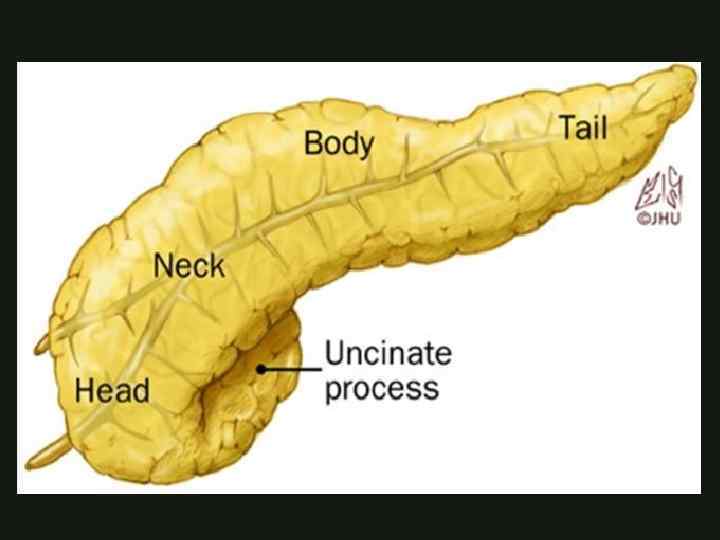

КЛАССИФИКАЦИЯ ОСТРОГО ПАНКРЕАТИТА По распространенности поражения: - мелкоочаговый - крупноочаговый По локализации: - с поражением головки - тела - хвоста - всех отделов поджелудочной железы

КЛАССИФИКАЦИЯ ОСТРОГО ПАНКРЕАТИТА По распространенности поражения: - мелкоочаговый - крупноочаговый По локализации: - с поражением головки - тела - хвоста - всех отделов поджелудочной железы